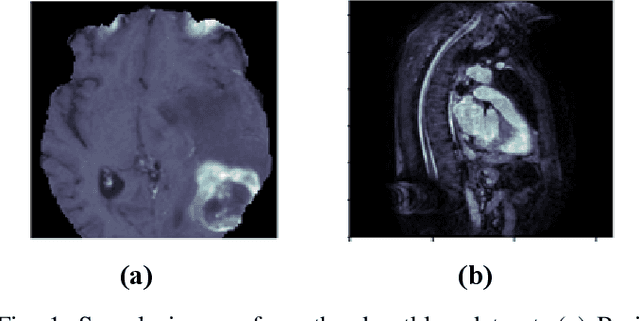

Abstract:Deep learning techniques, particularly convolutional neural networks, have shown great potential in computer vision and medical imaging applications. However, deep learning models are computationally demanding as they require enormous computational power and specialized processing hardware for model training. To make these models portable and compatible for prototyping, their implementation on low-power devices is imperative. In this work, we present the implementation of Modified U-Net on Intel Movidius Neural Compute Stick 2 (NCS-2) for the segmentation of medical images. We selected U-Net because, in medical image segmentation, U-Net is a prominent model that provides improved performance for medical image segmentation even if the dataset size is small. The modified U-Net model is evaluated for performance in terms of dice score. Experiments are reported for segmentation task on three medical imaging datasets: BraTs dataset of brain MRI, heart MRI dataset, and Ziehl-Neelsen sputum smear microscopy image (ZNSDB) dataset. For the proposed model, we reduced the number of parameters from 30 million in the U-Net model to 0.49 million in the proposed architecture. Experimental results show that the modified U-Net provides comparable performance while requiring significantly lower resources and provides inference on the NCS-2. The maximum dice scores recorded are 0.96 for the BraTs dataset, 0.94 for the heart MRI dataset, and 0.74 for the ZNSDB dataset.